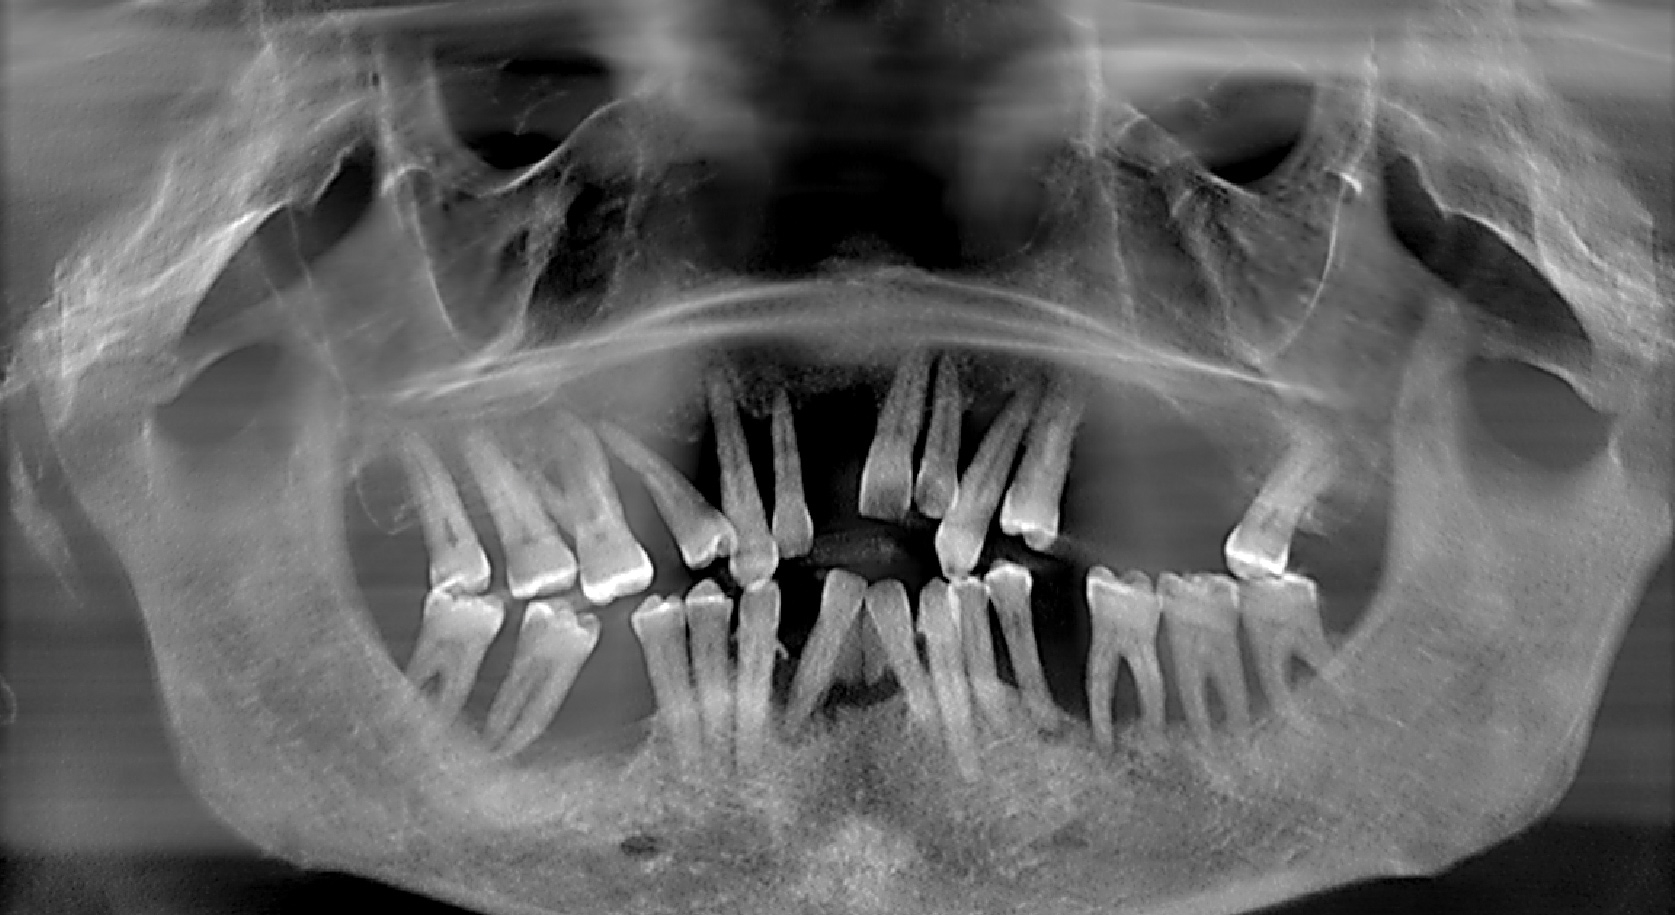

Teeth Exfoliating With Initial Impressions

Many patients requiring All-on-4–style treatment have extremely compromised teeth that may be unintentionally removed during the initial impression process. This is typically due to severely decayed teeth or extremely mobile teeth secondary to advanced periodontal disease (Figure 1). Such situations must be recognized and these patients advised of the potential for tooth loss during the impression process.

Fig 1. Presurgical panoramic radiograph of a patient with severe periodontal disease and who is an All-on-4–style treatment candidate.

Figure 1